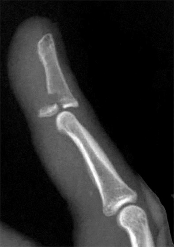

Figure 1 shows a radiograph obtained from an active 30-year-old man who sustained an injury to his ring finger 1 week earlier. The most appropriate treatment is

Figure 1 reveals evidence of an intra-articular distal phalanx fracture with a distal interphalangeal (DIP) joint dorsal subluxation. This injury is unstable and requires surgical management for an active individual. Volar distal phalanx fractures are often associated with flexor digitorum profundus avulsion injuries, which are addressed concomitantly. This injury was treated with ORIF of the intra-articular fracture, pinning of the DIP joint, and repair of an avulsed flexor digitorum profundus tendon with a button on the dorsal nail plate, as shown in Figure 2. Splint immobilization would not maintain a reduction of this unstable injury. The terminal tendon is not injured in this patient but is often injured in a dorsal distal phalanx fracture with a volar dislocation. Arthrodesis of the DIP is a salvage procedure and would not be considered acutely.